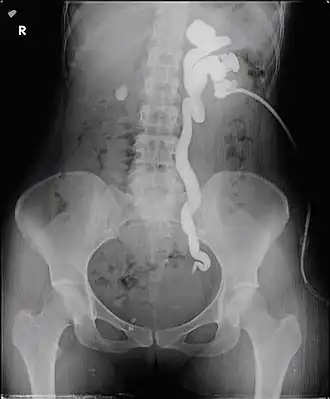

![]() Antegrade pyelogram of grade III hydronephrosis with obstruction at the ureterovesical junction due to bladder endometriosis in a 29 year old female. The tip of the nephrostomy is located in an inferior calyx. | |

Antegrade pyelography is the procedure used to visualize the upper collecting system of the urinary tract, i.e., kidney and ureter. It is done in cases where excretory or retrograde pyelography has failed or contraindicated, or when a nephrostomy tube is in place or delineation of upper tract is desired. It is commonly used to diagnose upper tract obstruction, hydronephrosis, and ureteropelvic junction obstruction. In this, radiocontrast dye is injected into the renal pelvis and X-rays are taken. It provides detailed anatomy of the upper collecting system. As it is an invasive procedure, it is chosen when other non-invasive tests are non confirmatory or contraindicated and patient monitoring is required prior and after the procedure.[11][12]